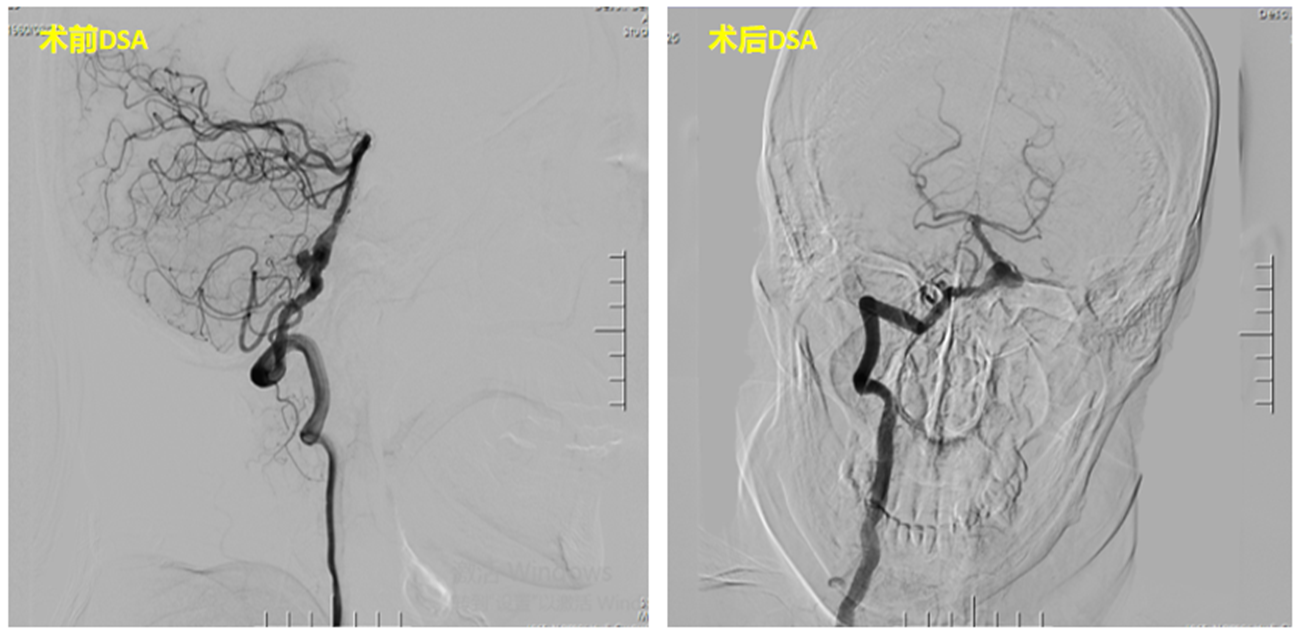

在赵大爷及家属的坚持下,吴善武主任带领专科团队对赵大爷的情况进行了专门的病例讨论,制定了详细周密的手术计划。最终,吴善武及其带领的专科团队没有辜负赵大爷的期望,手术非常成功,赵大爷在家属的陪同下顺利康复出院(如下图所示)。

动脉瘤直径<5、伴有自发性蛛网膜下腔出血病史,有家族史或需长期口服抗凝及抗血小板药物的动脉瘤患者,推荐积极手术治疗(包括开颅手术及血管内介入栓塞术)(如下图);未治疗的未破裂动脉瘤患者,建议对其进行动态随访,随访过程中发现动脉瘤进行性增大、形态改变者,建议进行手术;由于患有未破裂动脉瘤导致患者心理障碍,严重影响工作生活的可适当放宽手术指征,采取更加积极的治疗策略。